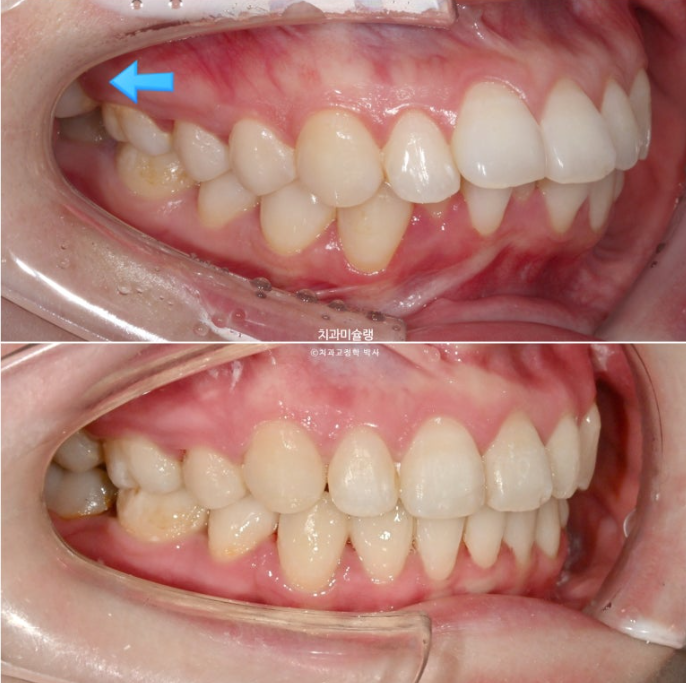

파란 화살표 부분은 위 아래 큰어금니가 엇갈려 물리는 가위교합입니다.

파란화살표 두번째 큰어금니가 바깥으로 밀려나가 가위교합이 된 것 입니다.

파란 화살표 큰어금니가 입천장쪽으로 들어오면서 가위교합이 해소가 되었습니다.

파란 화살표 부분의 가위교합이 개선이 되면서 어금니 교합은 물샐틈 없는1급 교합관계를 보입니다.

심하게 뻗쳐있던 앞니가 정상각도를 찾았습니다.

호두턱 (호두주름)으로 인하여 원래 있던 무턱이 실제보다 더 심해보였던 것이 개선이 되면서 턱라인 개선이 눈에 띕니다.

이제 비로소 입이 편하게 다물립니다.

입매는 과하지 않게 적정량 예쁘게 들어갔습니다.

돌출입이 해소가 되면 비순삭이 줄면서 코도 높아보입니다.

앞니가 뒤로 6mm 이상 들어갔고 통상 발치교정보다 더 많은 양이 들어갔지만, 교정 후 옥니 등 부작용은 보이지 않습니다.

입술 부전증 해소로 턱끝 힘이 풀리니 울퉁불퉁했던 턱라인이 매끈해 졌습니다.